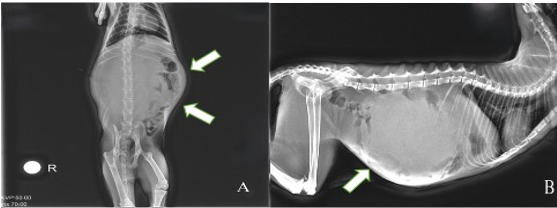

• Unilateral Perinephric Pseudocyst in a Young British Shorthair Cat: Diagnostic Imaging and Surgical Outcome

Emre Eren, Murat İlgün, Sıtkıcan Okur, Mustafa Sinan Aktaş

23-27

DOI: https://doi.org/10.71336/ijvar.676